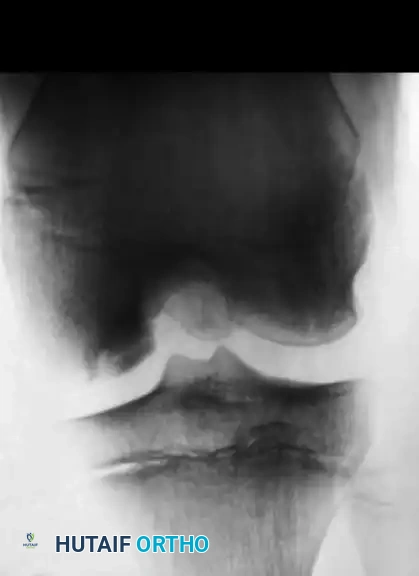

Image

As demonstrated in the clinical case above, an adolescent with an open physis and a stable lesion was treated nonoperatively in a cast for 9 months. Several years later, complete radiographic healing is apparent, and the knee is entirely asymptomatic. However, prolonged immobilization must be balanced against the risks of muscle atrophy and joint stiffness. Contemporary protocols favor hinged knee braces and strict cessation of sports rather than rigid casting.